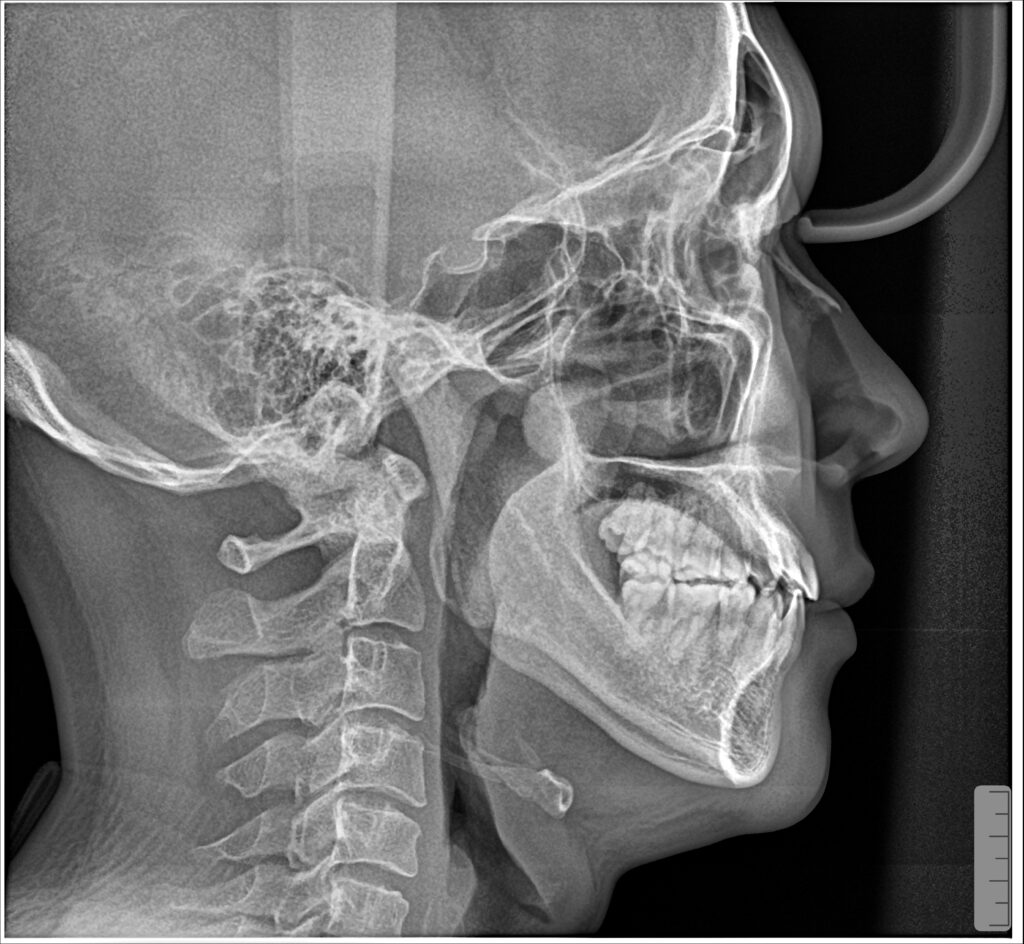

Lệch mặt hay MLD (lệch xương hàm dưới sang bên) là tình trạng cằm của BN lệch sang bên, không nằm trên đường giữa mặt làm khuôn miệng khi cười và thậm chí cả khi thả lòng đều lệch sang 1 bên. Tình trạng lệch này có thể căn nguyên do xương hai bên phát triển không cân, cũng có thể do sai khớp cắn làm bệnh nhân ăn nhai không đều hai bên dẫn đến lệch hàm. Với các trường hợp lệch do khớp căn (lệch xương hàm dưới chức năng) thì chỉnh nha có thể can thiệp niềng để tái lập lại đúng vị trí xương hàm dưới, đem lại kết quả tuyệt vời sau niềng. Với các trường hợp lệch do xương thì cần có chỉ định can thiêp phẫu thuật.

BN nam sinh năm 1994 khớp cắn hạng III, răng chen chúc. BN có sự phát triển không đồng đều của xương hàm dưới hai bên dẫn đến biến chứng lệch mặt. Kết hợp cả yếu tố sai khớp cắn do răng làm hàm dưới vừa lệch do xương lại vừa lệch do thích nghi chức năng. BN đã được nhổ 3R4 để giải quyết vấn đề chen chúc răng và kéo lùi nhóm răng cửa dưới.

Kết quả: đường giữa gần như thẳng, xương hàm dưới định vị về vị trí bình thường. Khuôn mặt cải thiện khá so với trước điều trị nhưng không thể hoàn hảo do căn nguyên sai lệch kết hợp đến từ sai lệch xương ![]()